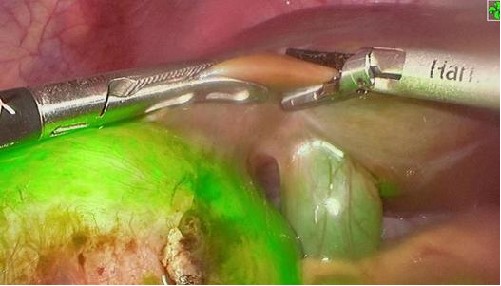

腦膠質(zhì)瘤是腦部最常見的原發(fā)性腫瘤,占中樞神經(jīng)系統(tǒng)惡性腫瘤的81%。目前,腦膠質(zhì)瘤的治療仍以手術(shù)為主導(dǎo)。然而,手術(shù)在完全切除腫瘤方面常面臨挑戰(zhàn),有時甚至難以實現(xiàn)。近年隨著熒光成像技術(shù)在惡性腦膠質(zhì)瘤精準(zhǔn)手術(shù)中的廣泛使用,使得瘤切除術(shù)腫瘤切緣可視化成為可能。但目前臨床常用的熒光造影劑存在給藥到手術(shù)時間不確定的問題,可能造成病灶與正常組織對比度不足,影響術(shù)中的病灶的判斷。

PL002是浙江普利藥業(yè)有限公司研發(fā)的熒光/磁共振雙模態(tài)造影劑,熒光/磁共振雙模態(tài)造影劑的成功研發(fā)將成為提高腦膠質(zhì)瘤手術(shù)效率的有效方案。術(shù)中熒光技術(shù)與核磁共振成像的結(jié)合,相較于單獨使用,能夠更準(zhǔn)確地識別腫瘤組織與功能區(qū)的位置關(guān)系,以及患者的腫瘤浸潤邊緣。這種聯(lián)合使用不僅能在保留患者功能的前提下實現(xiàn)功能區(qū)腦膠質(zhì)瘤的最大限度安全切除,還能有效降低術(shù)中神經(jīng)損傷的風(fēng)險。

去年10月,PL002已經(jīng)獲得FDA簽發(fā)的美國藥物臨床試驗批件,用于原發(fā)性肝癌患者的術(shù)前診斷及術(shù)中導(dǎo)航。此次在國內(nèi)申報的適應(yīng)癥為腦膠質(zhì)瘤患者的術(shù)前診斷及術(shù)中導(dǎo)航。相較于原發(fā)性肝癌,腦膠質(zhì)瘤對于切除精度要求更高,尤其是臨近重要功能區(qū)的時候,因此對精準(zhǔn)診斷的造影劑的臨床需求更為迫切。